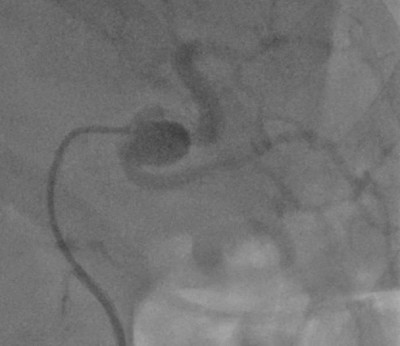

При большой или быстро растущей аневризме, при угрозе разрыва выбирается оперативное вмешательство. Предпочтение отдаётся малоинвазивным методам: эндоваскулярной (внутрисосудистой) хирургии: стентированию и эмболизации САС — закрытие полости выпячивания с помощью специальных материалов или препаратов. Вмешательства проводятся под рентген-контролем.